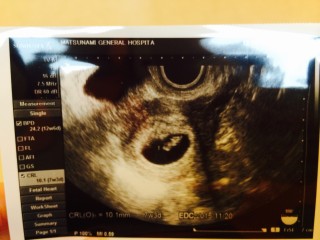

前の健診では、赤ちゃんの入ってる袋だけしか見えなかったのに たったの2週間で、しっかり形ができていてびっくりしました! 心拍の確認もできて、嬉しかったです。 赤ちゃんは9.1mmで 次の健診で、出産予定日が決まるそうです。